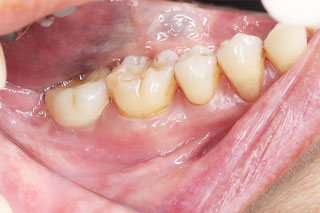

口腔内写真

BEFORE

左下と右下の奥歯に被せ物が入った状態です。